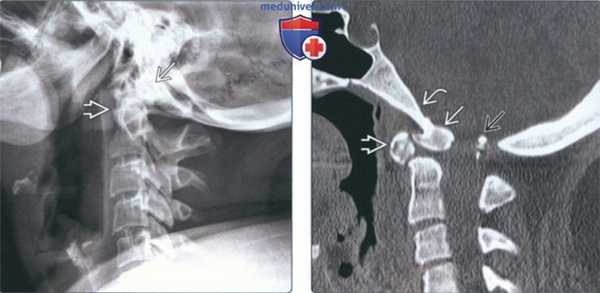

(Слева) На рентгенограмме шейного отдела позвоночника в боковой проекции определяется врожденная гипоплазия зубовидного отростка без нарушения соотношения С1/С2. Передняя дуга С1 слегка увеличена, скорее всею, за счет компенсаторной гипертрофии. Другие аномалии шейного отдела позвоночника отсутствуют.

(Справа) На рентгенограмме шейного отдела позвоночника в боковой проекции определяется легкая гипоплазия зубовидного отростка с компенсаторным увеличением передней дуги С1. Соотношения в краниовертебральном переходе не изменены, другие аномалии отсутствуют.

(Слева) На сагиттальной КТ с КУ (спондилометафизарная дисплазия) определяется гипоплазия зубовидного отростка и С1, приводящая к стенозу позвоночного канала. Передняя дуга атланта образована хрящом вследствие патологической задержки окостенения.

(Справа) На сагиттальной MPT (Т2 ВИ) (нейроэнтерическая киста) определяются врожденные аномалии костей краниовертебрального сочленения, в т.ч. укорочение и дисплазия зубовидною отростка. Смещение передней дуги С1 кпереди отражает атланто-аксиальную нестабильность.